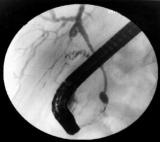

ERCP පරීක්‍ෂණය

ERCP පරීක්‍ෂණයක් යනුවෙන් අදහස් කරන්නේ කුමක්ද?

මෙය එන්ඩොස්කොපි පරීක්‍ෂණයකි. මෙහිදී සාමාන්‍ය එන්ඩොස්කොපි පරීක්‍ෂණයකට වඩා සිදුකරනුයේ පිත්නාල පරීක්‍ෂා කිරීමකි. ඊට අමතරව එක්ස්රේ ගැනීමද සිදුකරයි. නමුත් මෙය සාමාන්‍ය එන්ඩොස්කොපි පරීක්‍ෂණයකට වඩා සංකීර්ණ වන අතර වැඩි වේලාවක් ගත වේ. ඊට අමතරව නිදිමත ගතිය ඇතිවීමට ඖෂධ දීමද සිදුකරයි.